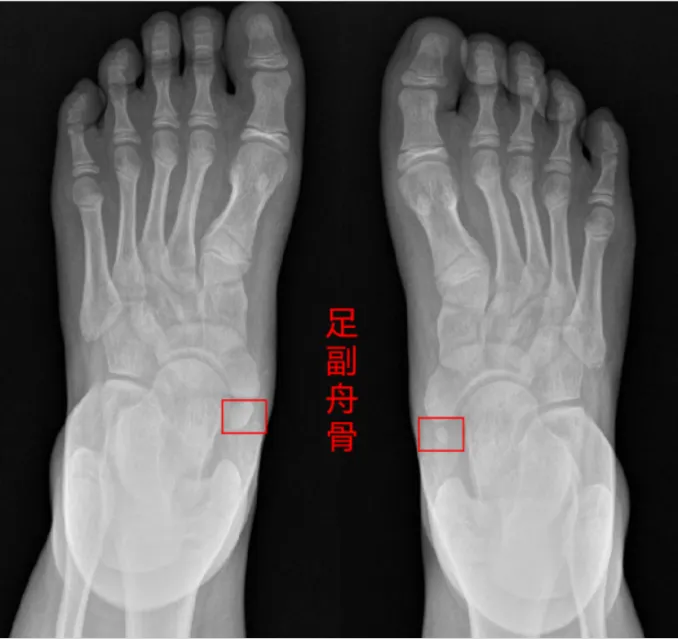

是的,这块多出来的骨头叫——足副舟骨。

来认识一下:

足舟骨:我们每个人脚上都有一块叫足舟骨的骨头,它是一块正常的骨头。

副舟骨:副舟骨就是正常的足舟骨旁边,多长了一块本不应存在的小骨头。有点像长了“智齿”,不过是在脚上。

拍一张足部X光片

就能看清楚

是不是多了这块“脚上智齿”